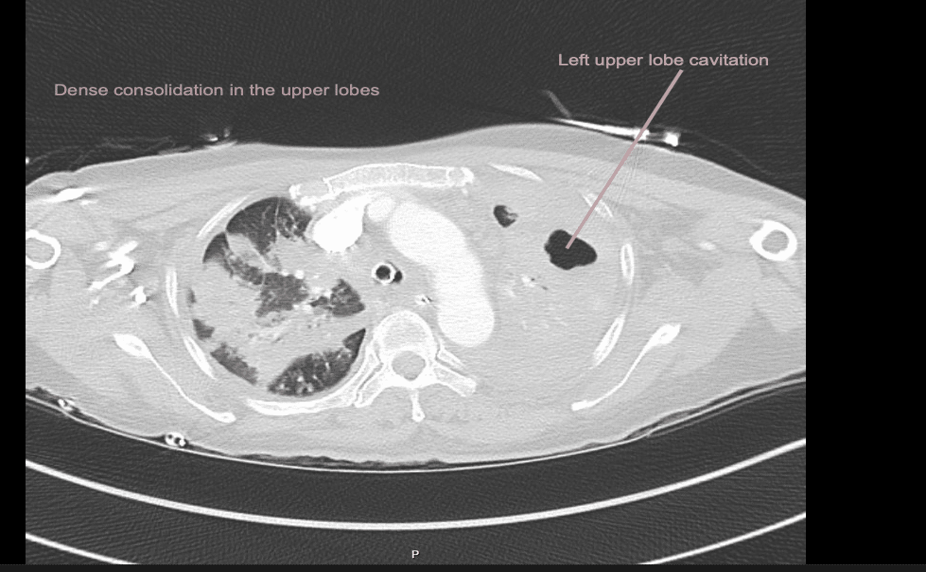

EXPLANATION -There is diffuse bilateral consolidation more prominent in the upper lobes.

There is left upper lobe cavitation. Bilaterally there are pleural effusions.